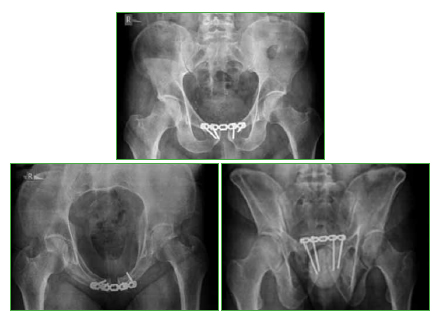

Flegmasia cerúlea dolens posquirúrgica inmediata en el tratamiento de una fractura de pelvis. Reporte de Caso